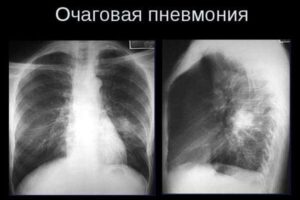

Для пневмонии характерна осенне-зимняя сезонность, когда высок риск переохлаждения и ослабления иммунитета в период повышенной заболеваемости ОРЗ и гриппом. Правосторонняя пневмония — наиболее частый вариант развития болезни, что обусловлено анатомическим строением бронхиального дерева. Об этом мы и поговорим в сегодняшней статье. Отличие от левосторонней Правосторонняя пневмония — это результат воспалительного сбоя при попадании инфекции в …